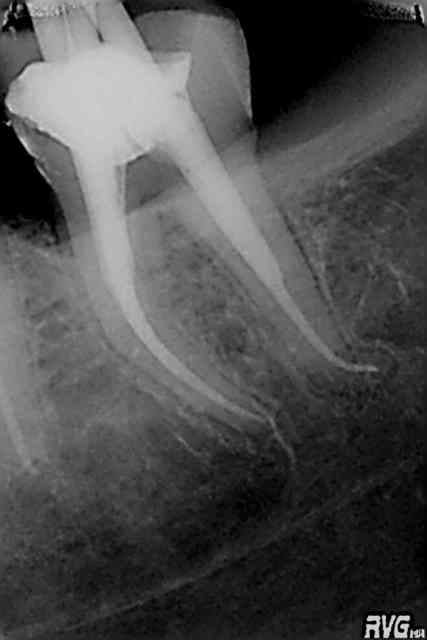

R23 qq9nvn - Eugenol

R30 tnef0w - Eugenol

R31 rguuok - Eugenol

R32 osoz98 - Eugenol